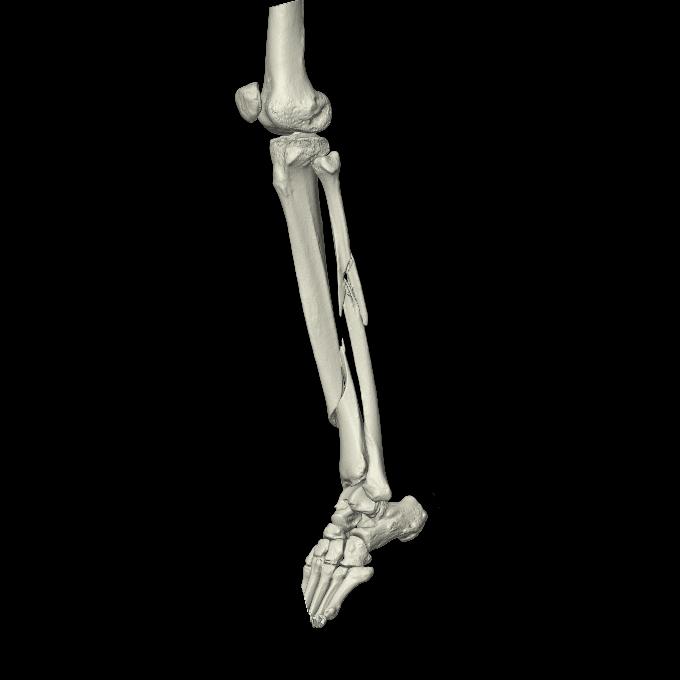

110211 1/6 1/8 左前腕 4R 15歳男性 橈骨骨幹部骨折